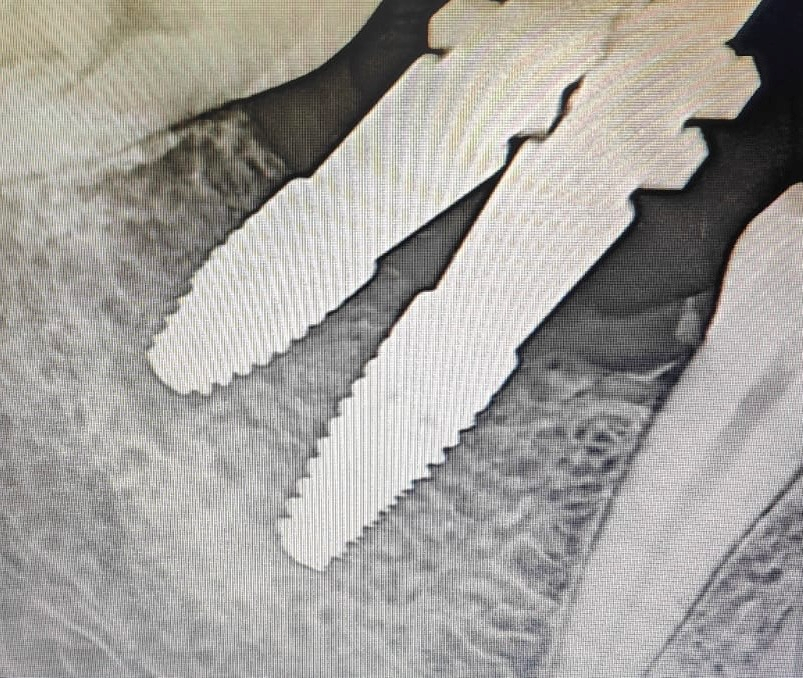

The various prosthetic treatment options for malpositioned implants are outlined in Table 1. Malpositioned implants may result from multiple surgical and prosthetic errors; Figures 1–3 highlight the various positional errors encountered in dental implant placement.

Figure 3. Periapical infection near dental implant.